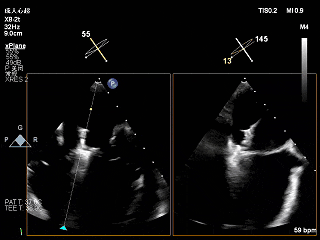

全麻下穿刺右股静脉,在TEE指导下完成房间隔穿刺,穿刺处与二尖瓣瓣环距离3.85cm。将superstiff导丝送至左房,应用18F鞘管扩张穿刺部位,沿导丝将可操控导引导管送入左肺静脉。

将“大鞘”送入左房

3D下大鞘的穿刺位置大概在3点钟方向

左房较大,完成骑跨